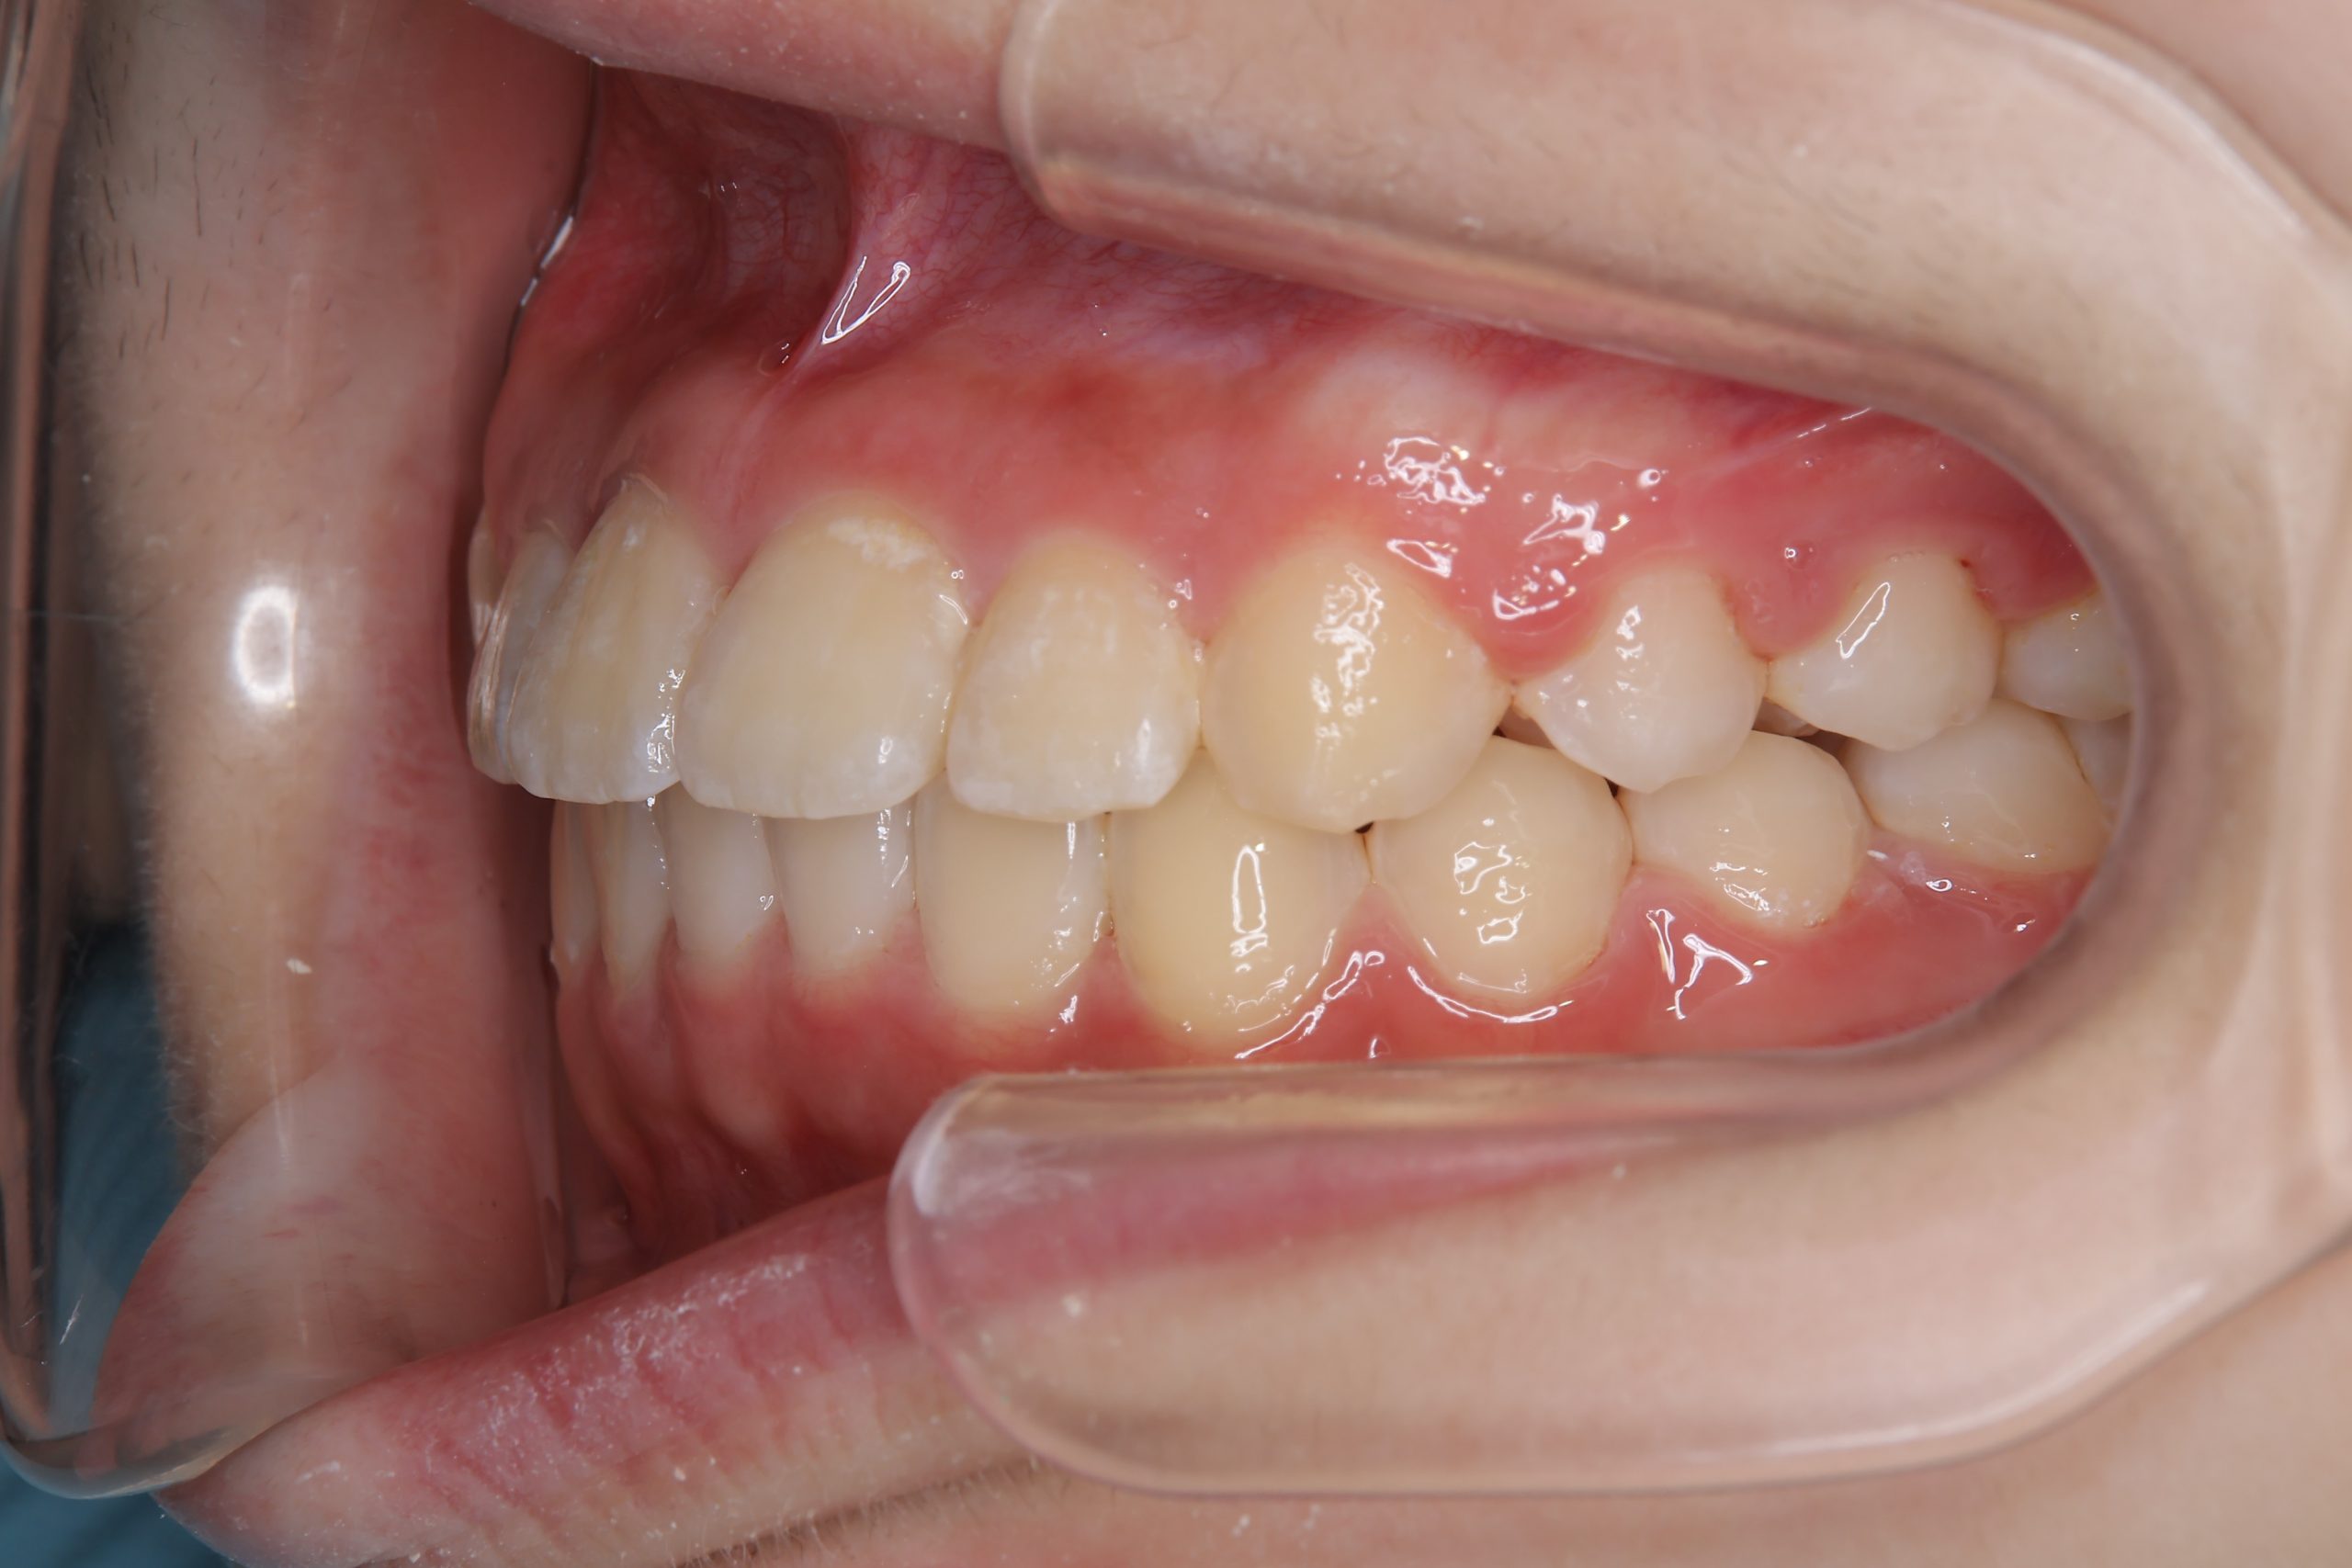

全顎ワイヤー矯正 症例_805 Case

ビフォー

アフター

主訴 中心から前歯がずれている

施術内容 成人矯正1期治療

治癒期間 1年3か月間

費用 954,800円(税込)

リスク・副作用 違和感、不快感、痛み